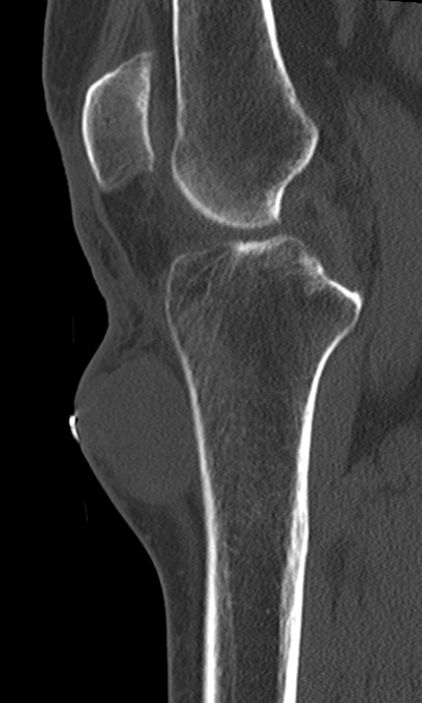

| Fall | CT: Rundliche, kapsulierte, glatt begrenzte RF an der proximalen Tibia medialseitig 3 cm.

Keine Infiltration der Haut oder der Tibia.![]() |